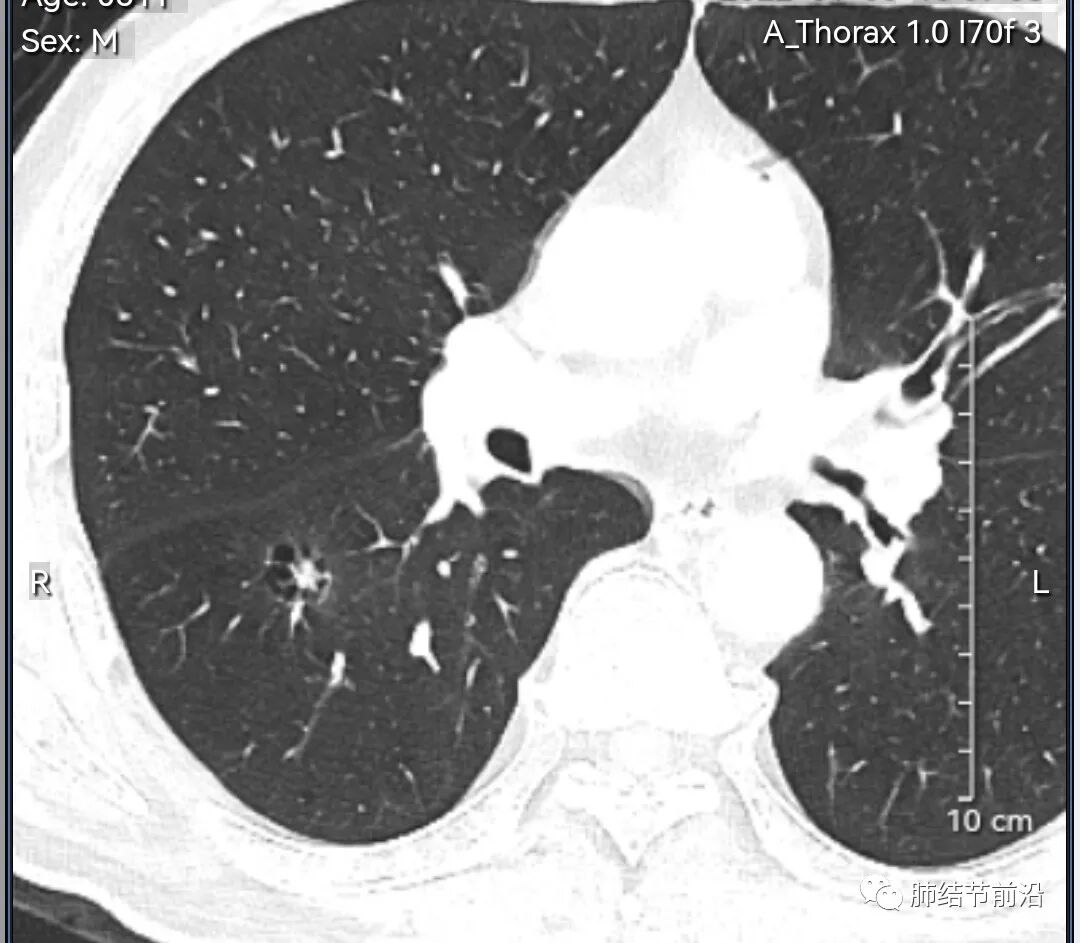

男性,67岁,重度吸烟史。CT发现右下肺囊腔。来看一下这个CT的特点:

该囊腔形态非常有特点,和常见的圆形肺大泡有很大的区别。

1.囊腔中央实性成分,周围有磨玻璃影。

2.囊腔中央有血管。

3.囊腔外周有分叶形态。

4.囊腔有胸膜牵拉。

出现这几种形态,CT可以确认恶性的腺癌。这个囊腔形成的机制,为肿瘤实性成分堵塞细支气管形成活瓣,肺泡内压力增高破裂行成,因此肺内血管成分保留。由于肺泡压力增高,而呈分叶状。另外,也有肿瘤的胸膜牵拉这一特点。

囊腔周围磨玻璃+囊腔中央血管为特征性表现。如果持续存在,几乎可以100%确认为早期肺腺癌。

建议患者手术切除,术后病理为浸润性腺癌,腺泡型,部分为实体型。IA1期,术后不用治疗。